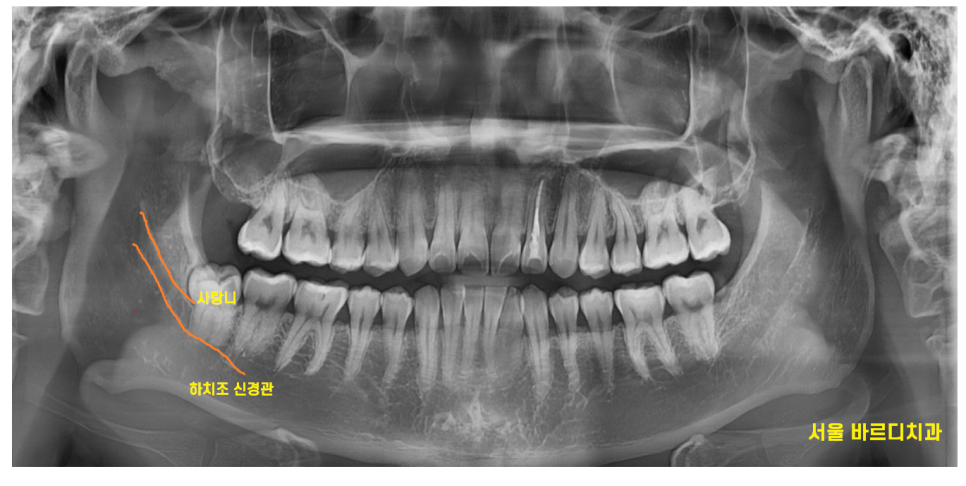

X-RAY부터 찍어보았는데요

아래 사랑니의 최대의 적

하치조 신경관과 딱! 붙어있네요.

자세한 것은 CT를 한장 찍어보기로 하고